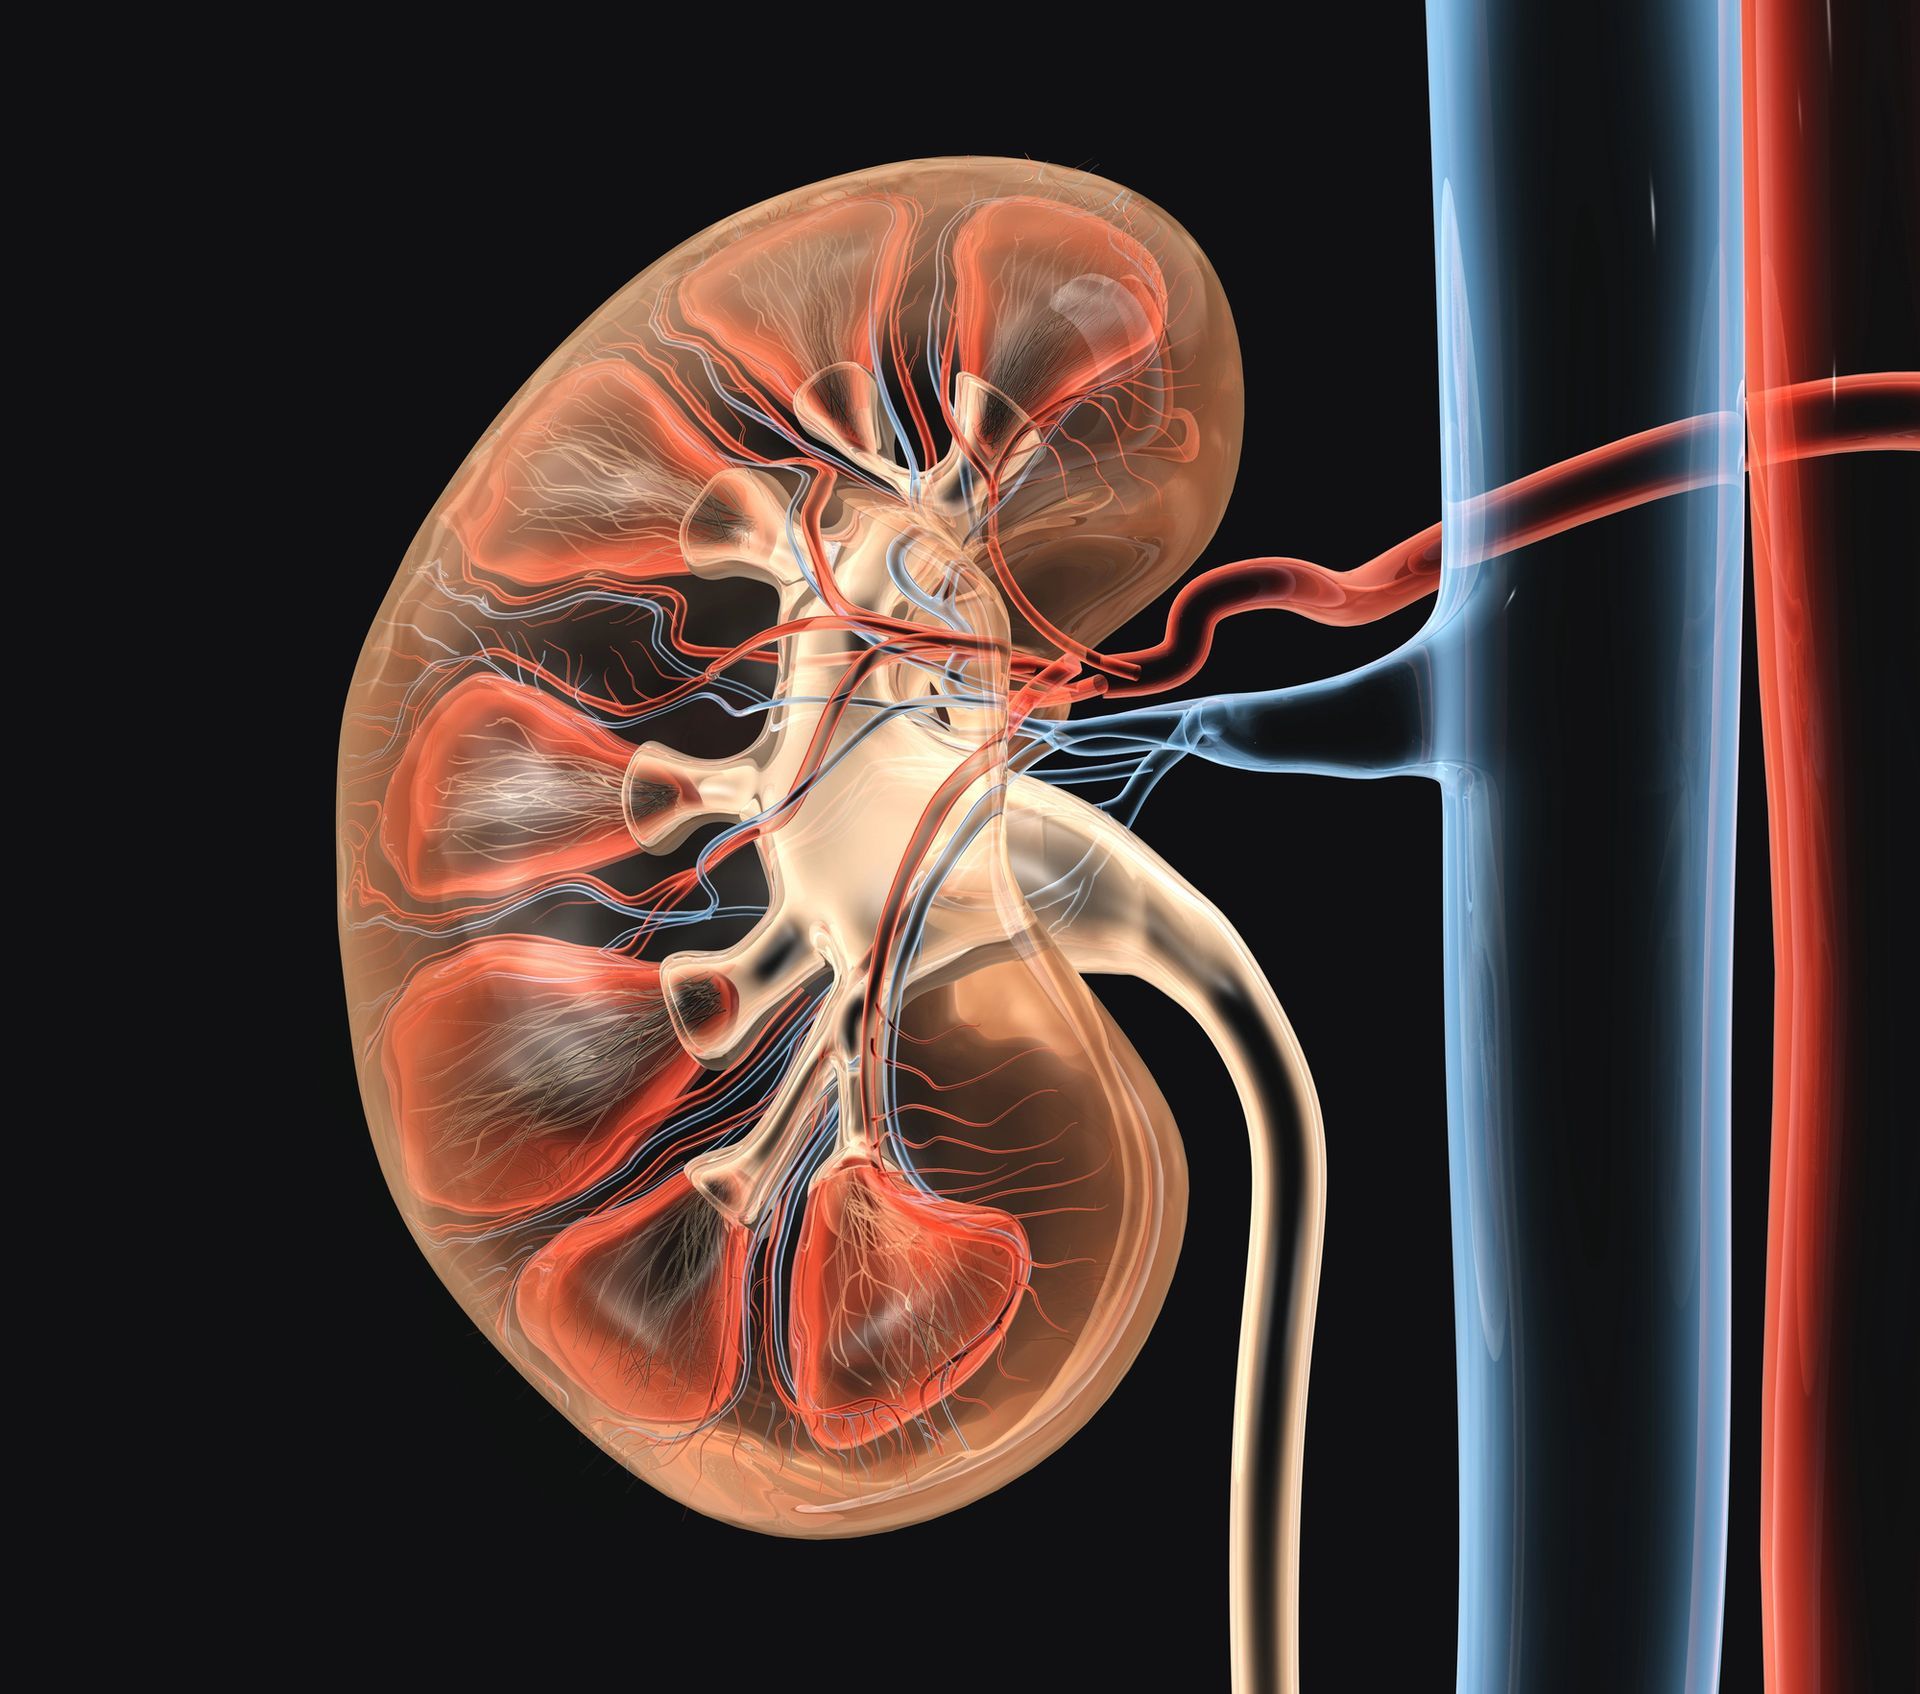

L’Uro TC rappresenta una delle metodiche più efficaci per lo studio dell’apparato urinario, grazie alla combinazione tra le potenzialità diagnostiche della tomografia computerizzata e l’uso del mezzo di contrasto. Questo esame consente di analizzare in modo dettagliato reni, ureteri e vescica, offrendo una valutazione completa sia della struttura anatomica sia della funzionalità delle vie urinarie. L’impiego dell’Uro TC si affianca all’urografia tradizionale, una procedura radiologica che da anni permette ai medici di osservare con precisione le condizioni dell’apparato urinario attraverso immagini radiografiche sequenziali. Le due metodiche, differenti ma complementari, consentono di ottenere un quadro diagnostico organico e accurato, fondamentale nella gestione di disturbi come calcolosi, infiammazioni, sospette ostruzioni o presenza di sangue nelle urine. Presso il Centro Diagnostico Città di Casarano entrambe le indagini vengono eseguite da personale qualificato e con attrezzature specifiche, garantendo comfort e sicurezza lungo tutta la procedura.

Uro TC: tecnologia avanzata per la valutazione dell’apparato urinario

L’Uro TC è una metodica evoluta che sfrutta la tomografia computerizzata per produrre immagini ad alta definizione delle vie urinarie dopo somministrazione del mezzo di contrasto. A differenza dell’urografia convenzionale, la Uro TC consente una visione tridimensionale delle strutture anatomiche, con un livello di dettaglio estremamente elevato. La procedura è completamente indolore e dura in media una quindicina di minuti. Dopo l’accoglienza, il paziente viene posizionato sul lettino in decubito supino, con le braccia leggermente flesse sopra la testa. Il radiologo somministra il mezzo di contrasto endovena, che può provocare un transitorio sapore metallico in bocca, considerato del tutto normale.

Una volta avviato l’esame, il lettino scorre all’interno dell’apparecchiatura radiogena aperta alle estremità, dove vengono effettuate le scansioni successive. L’Uro TC permette non solo di osservare la morfologia di reni, ureteri e vescica, ma anche di valutare la funzionalità del sistema urinario, poiché il mezzo di contrasto evidenzia eventuali variazioni del flusso, malformazioni o alterazioni della struttura. È un esame particolarmente indicato in caso di ematuria, sospetti calcoli, traumi, o quando è necessario integrare informazioni ottenute da indagini precedenti. Per garantire una corretta esecuzione, il paziente deve essere a digiuno da almeno otto ore. Terminata la procedura, è consigliato bere abbondante acqua per favorire l’eliminazione del mezzo di contrasto.